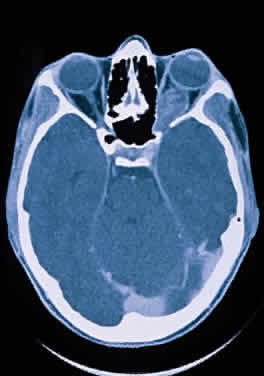

The optic nerve is affected in some manner in 1% to 5% of patients with sarcoidosis and is the second most frequently involved cranial nerve—the facial nerve being the most common.67,68 Rarely, sarcoidosis may present as tumefactive enlargement of the optic nerve without evidence of systemic disease. Most cases are misdiagnosed initially as meningioma or orbital pseudotumor (Figs. 50 and 51).67,69

Fig. 50. Bilateral thickening of the optic nerve and sheaths due to sarcoidosis. Computed tomography.

Fig. 51. Sarcoidosis of the optic nerve. Noncaseating granulomas replace the optic nerve parenchyma (low power, left; high power, right).